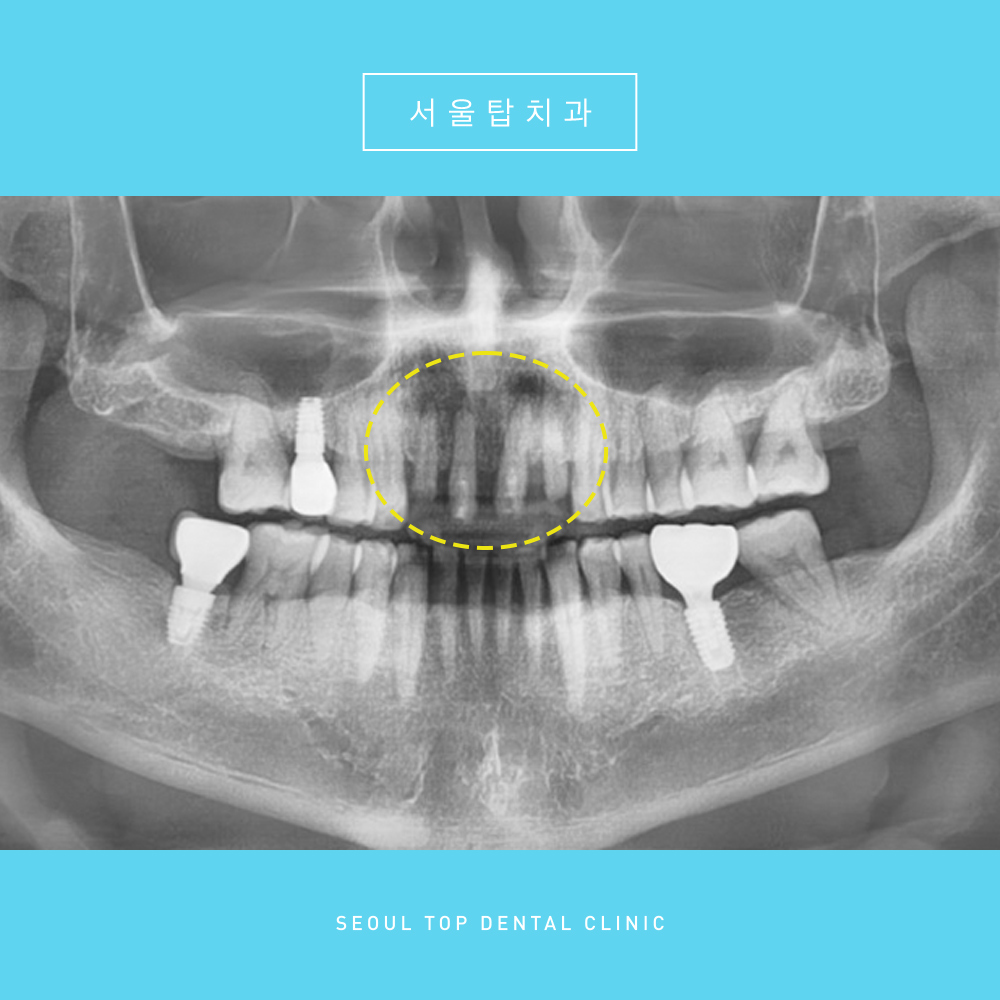

총 4개를 발치하였는데,

임플란트는 2개를 식립하고 중간에 인공치를 달아

브릿지의 형태로 임플란트 치료를 도와드렸습니다.

말을하거나 웃을때 눈에 띄는 앞니 부분이라

심미적인 부분도 고려하여

보철물의 색상 및 형태, 크기 등을 더욱 더 신경써

치료를 잘 마무리해드렸습니다.

앞니임플란트 치료 전, 후 사진입니다.

치료를 성공적으로 잘 마무리해드렸습니다.